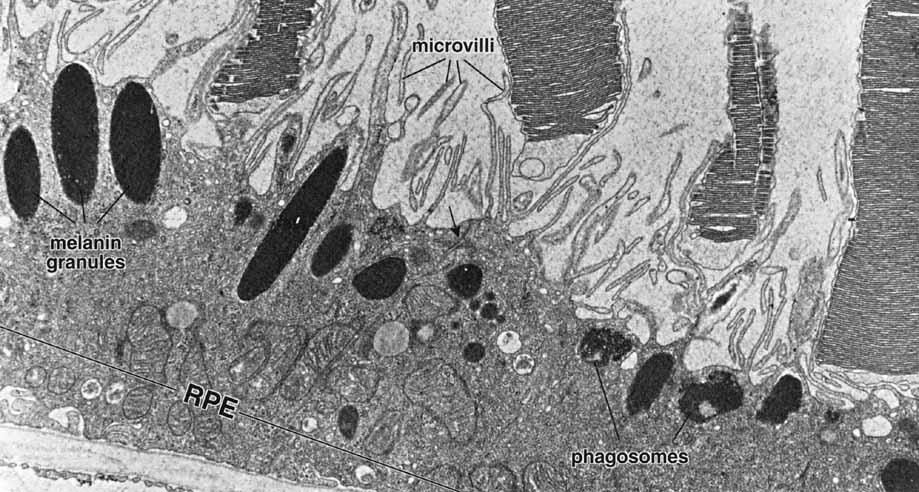

Fig. 4 Electron micrograph of the retinal pigment epithelium in association with the outer segments of rods and cones. Retinal pigment epithelium (RPE) contains numerous elongated melanin granules that are aggregated in the apical portion of the cell, where the microvilli extend from the surface toward the outer segments of the rod and cone cells. The retina pigment epithelial cells contain numerous mitochondria and phagosomes. The arrow indicates the location of the junction complex between two adjacent cells, ×20,000. (Courtesy of Dr. Toichiro Kuwabara and reproduced from Ross et al. 2003)

As already discussed, the topography of retinal development results in the intimate association of RPE apical microvilli with rod and cone photoreceptor outer segments across the intraretinal space (Figs. 4 and 6). These are bound together by the interphotoreceptor matrix (IPM), a network of proteins and proteoglycans containing a variety of enzymes, growth factors, carrier proteins, and other constituents.4 A number of constituents of this matrix have been localized in three distinct patterns, such as those that demonstrate rod- and cone-specific localization, those with an apical-to-basal heterogeneity, and others with a more homogeneous distribution. When there is a neurosensory retinal detachment, the potential interphotoreceptor space expands as fluid accumulates to form what is clinically referred to as the subretinal space, and the photoreceptors, now deprived of their supportive RPE functions, will degenerate if re-attachment is not effective. To maintain normal retinal attachment, RPE cells develop long slender apical microvilli of 5 to 7μm in length, forming sheaths that appear to participate in phagocytosis of outer segments. Villous processes surrounding rods contain smooth endoplasmic reticulum, ribosomes, melanin granules, and actin filaments. Villous processes that surround extrafoveal cones are usually devoid of intracellular organelles except for pigment granules. Despite their intimate relationship, no junctional attachments have been found between the RPE apical processes and the photoreceptor outer segments, although several molecular mechanisms forming the basis of this recognition and adhesion have been proposed, as discussed later.